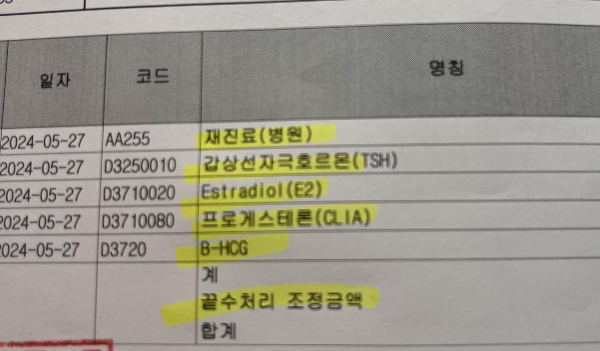

1. 진료비세부내역서

2. 진료비계산서

3. 처방전

이 세가지 서류 준비하시고, 전체 서류가 나오게 사진을 찍어서 각 실손보험 앱 또는 팩스로 환급 신청하시면 됩니다.

제가 산부인과 검진 항목 중 실비 환급 받았던 검진 항목은 아래와 같습니다.

1. 진료비 (약 2만 원)

2. 혈액검사비 (약 2-3만 원)

3. 질초음파 또는 복부초음파 (약 6만 원) *어떤 목적인지 중요합니다. 청구하실 때 질환에 의한 청구여야 합니다.

4. 균검사 (약 6만 원) *질염 또는 자궁경부 염증으로 인해 균검사 했을 때 해당 비용 환급받았음.